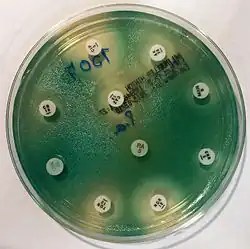

Many P. aeruginosa isolates are resistant to a large range of antibiotics and may demonstrate additional resistance after unsuccessful treatment. It should usually be possible to guide treatment according to laboratory sensitivities, rather than choosing an antibiotic empirically. If antibiotics are started empirically, then every effort should be made to obtain cultures (before administering the first dose of antibiotic), and the choice of antibiotic used should be reviewed when the culture results are available.

Due to widespread resistance to many common first-line antibiotics, carbapenems, polymyxins, and more recently tigecycline were considered to be the drugs of choice; however, resistance to these drugs has also been reported. Despite this, they are still being used in areas where resistance has not yet been reported. Use of β-lactamase inhibitors such as sulbactam has been advised in combination with antibiotics to enhance antimicrobial action even in the presence of a certain level of resistance. Combination therapy after rigorous antimicrobial susceptibility testing has been found to be the best course of action in the treatment of multidrug-resistant P. aeruginosa. Some next-generation antibiotics that are reported as being active against P. aeruginosa include doripenem, ceftobiprole, and ceftaroline. However, these require more clinical trials for standardization. Therefore, research for the discovery of new antibiotics and drugs against P. aeruginosa is very much needed. Antibiotics that may have activity against P. aeruginosa include:

As fluoroquinolones are one of the few antibiotic classes widely effective against P. aeruginosa, in some hospitals, their use is severely restricted to avoid the development of resistant strains. On the rare occasions where infection is superficial and limited (for example, ear infections or nail infections), topical gentamicin or colistin may be used.